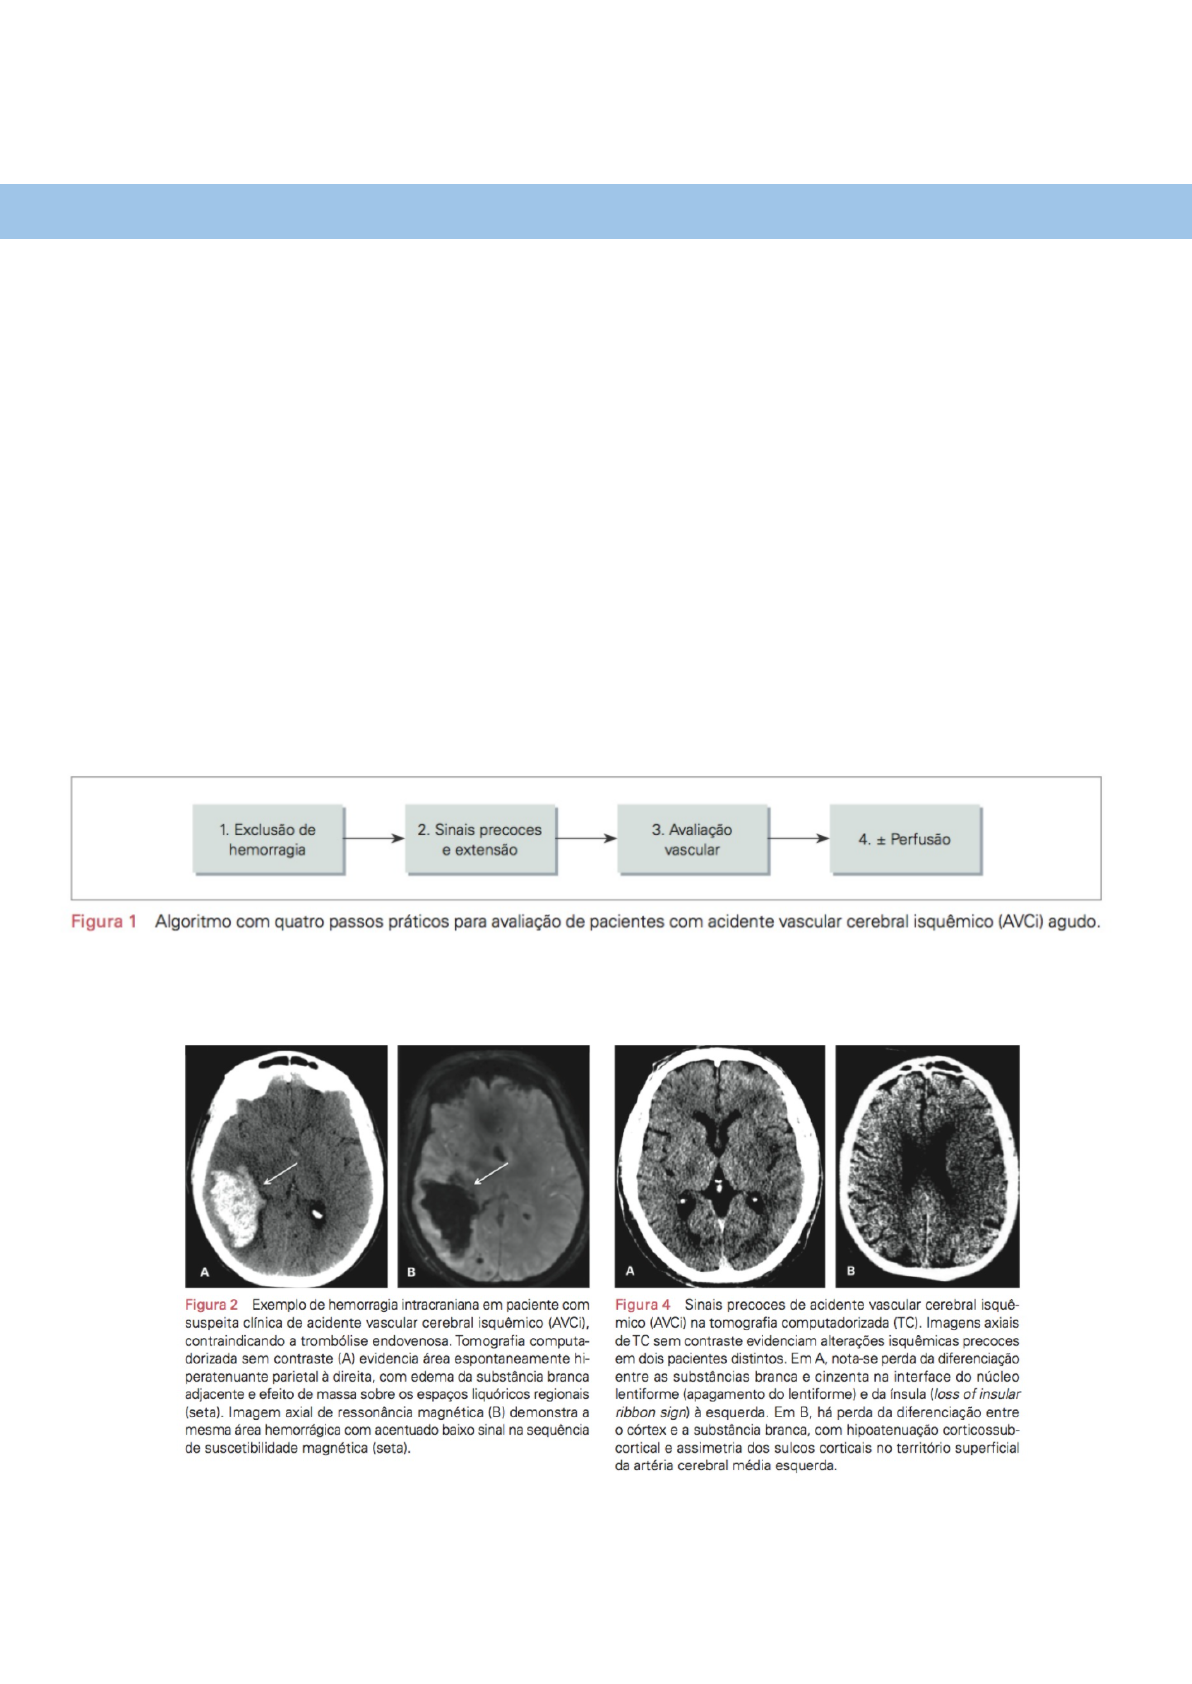

1. Exclusão de hemorragia

➔ TC exame padrão, exclui também tumores e infecções

➔ RM é mais sensível, mas a TC costuma ser mais prática

2. Sinais precoces e extensão

➔ Na TC: perda da diferenciação de substância branca e cinzenta, apagamento do núcleo lentiforme e da ínsula, hipoatenuação

do parênquima cerebral, edema adjacente, assimetria dos sulcos corticais